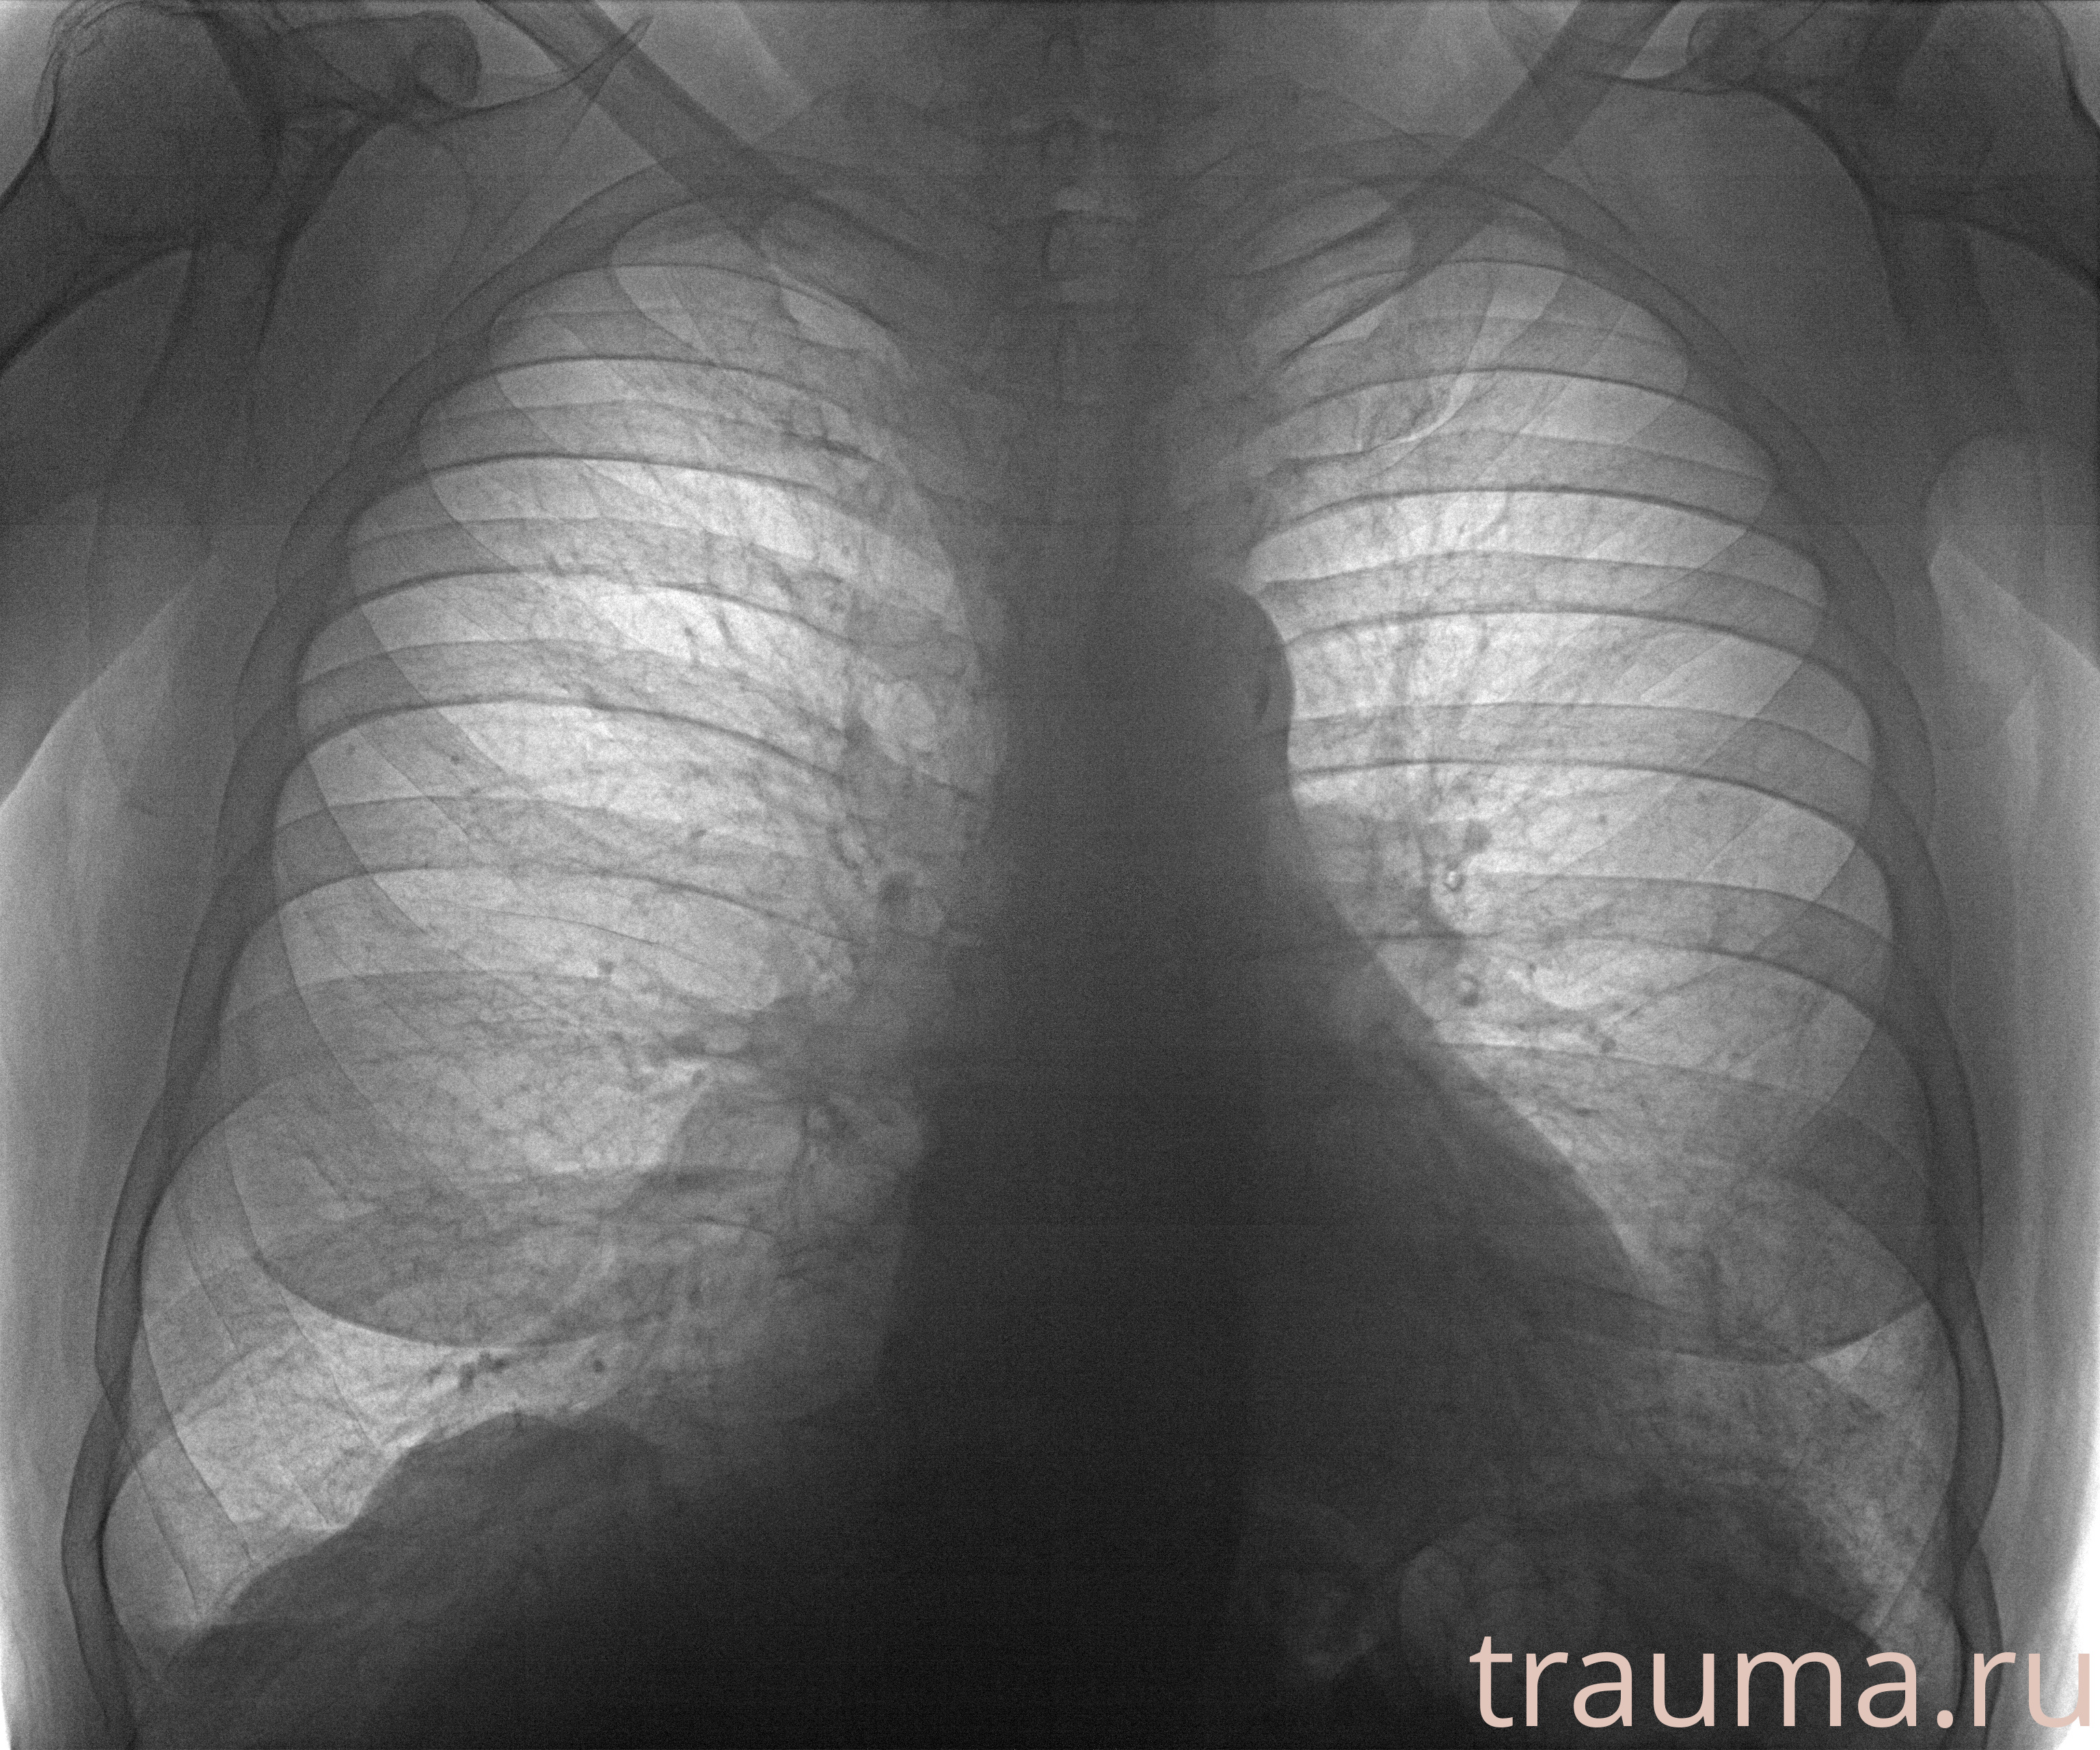

Рентгенограммы

Рентген на дому: по вашему адресу приезжает врач-рентгенолог, травматолог-ортопед с мобильным рентгеновским аппаратом, проводит диагностику травмы или заболевания, делает необходимые рентгенограммы, дает рекомендации по дальнейшему лечению. Получить качественные снимки в домашних условиях возможно благодаря уникальной методике, разработанной МосРентген Центром для института  Склифосовского

при переломе шейки бедра и пневмонии от компании МосРентген Центр - партнера Института имени Склифосовского